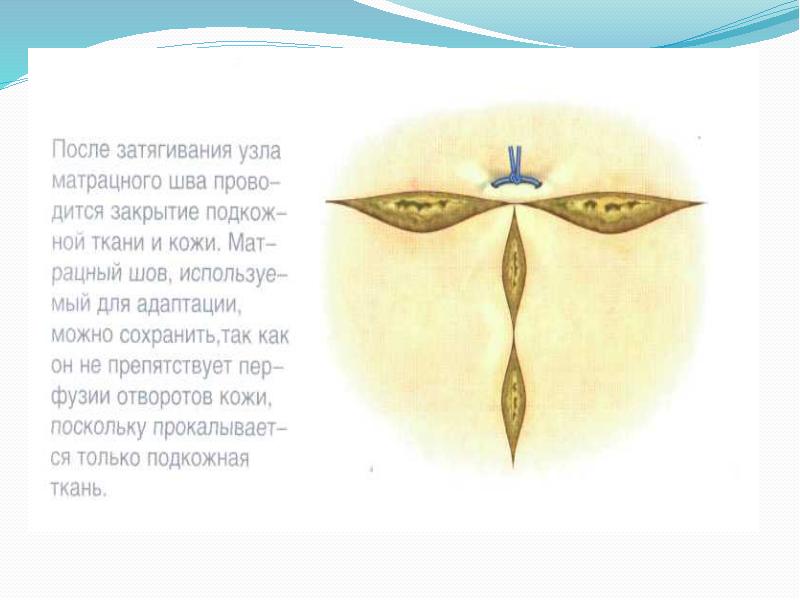

- 46. Зашивание асимметричных ран